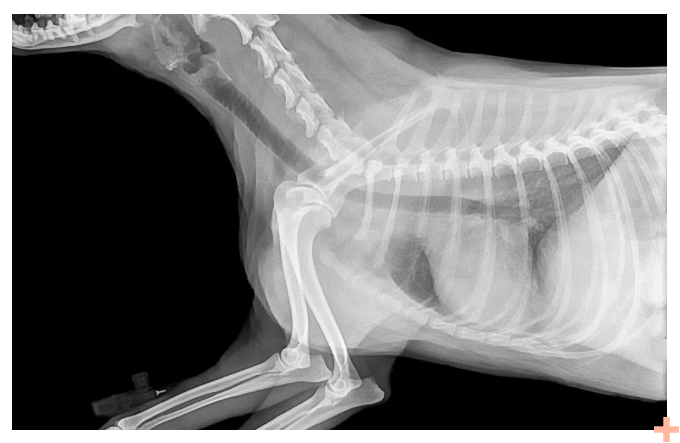

当患者患有实质脏器(如肝脏、肾脏)的肿瘤或肿瘤做完治疗后;或者患有比较严重的冠心病,需对冠状动脉的阻塞程度进行判断;或者有脑血管异常需要进一步确认......这些情况常需要通过造影检查来判断病变程度。

进行造影前需要服用或注射造影剂来摄入含原子序数高的元素物质,增强影像观察。一般造影剂可以分为钡剂、碘剂、气体等。

其中,碘化钠适用于膀胱造影、逆行尿路造影及手术后“T”管胆道造影。

通常,碘化钠会配制成12.5%的水溶液作造影剂。而且,为了减少因碘离子析出而对组织器官产生的刺激作用,有时会在碘化钠制剂内加入适量阿拉伯胶配成复方碘化钠溶液,以减少刺激并增强造影效果。

另外在临床上,在造影前做局部麻醉,注射或在造影剂中混入少量盐酸普鲁卡因,也可以减轻碘化钠溶液的刺激性给病人造成的痛苦。